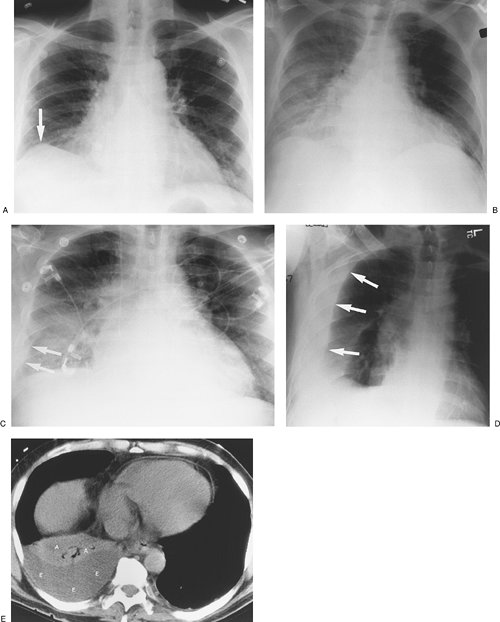

FIGURE 9-11. Malignant pleural effusion. A: PA chest radiograph of a 62-year-old woman with metastatic breast cancer who has had a right mastectomy and axillary node dissection (note surgical clips in right axilla; arrows) shows apparent elevation of the right hemidiaphragm. B: Lateral chest radiograph also shows apparent elevation of the right hemidiaphragm (arrows). The left hemidiaphragm is easily identified (arrowheads), as it is just superior to the stomach bubble. C: CT shows a large right pleural effusion (E) and metastatic breast cancer infiltrating the right chest wall (arrows). D: CT at a level inferior to (C) shows a metastatic soft tissue mass to the mediastinal pleura (arrow) and thickening of the mediastinal pleura (arrowheads).

When a large unilateral effusion is present (Fig. 9-11), four causes should be considered: (i) infection (empyema); (ii) tumor (primary bronchogenic carcinoma, mesothelioma, metastases, and lymphoma); (iii) chylothorax (secondary to tumor, most notably lymphoma, or ruptured thoracic duct); and (iv) hemorrhage (usually from trauma, whether iatrogenic or otherwise) (Table 9-2). Following drainage of a pneumothorax or pleural effusion, the re-expanded lung may become acutely edematous. The edema usually develops within 2 hours of re-expansion, can progress for 1 or 2 days, and resolves within 5 to 7 days. Large pleural collections with complete collapse

of the underlying lung, especially when long-standing, predispose to the development of re-expansion pulmonary edema (Fig. 9-12).

FIGURE 9-12. Re-expansion pulmonary edema. A: PA chest radiograph of a 78-year-old woman with metastatic breast cancer shows a large left pleural effusion associated with collapse of the left lung and shift of the mediastinum to the right. These findings suggest tension hydrothorax. B: PA chest radiograph after placement of a left chest tube and adequate drainage of pleural fluid shows re-expansion pulmonary edema on the left.

FIGURE 9-13. Tuberculous empyema. PA chest radiograph shows a large left pleural effusion. A large unilateral pleural effusion is worrisome for empyema, hemothorax, malignancy, or chylothorax.

FIGURE 9-14. Empyema. A: PA chest radiograph of a 60-year-old man with right lower lobe pneumonia shows a large right hydropneumothorax with air–fluid level. There is an incidental calcified granuloma in the right mid lung. B: CT shows a round collection of air and fluid in the right pleural space. The thickened and enhancing separated pleural layers create the "split pleura" sign. Air within an empyema can be secondary to thoracentesis, bronchopleural fistula, or, rarely, a gas-forming organism.